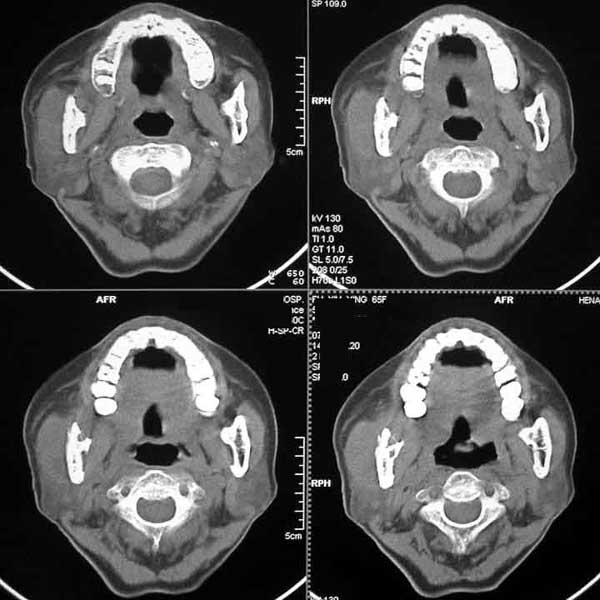

CT00208:下颌骨病变,有病理

(结果公布:http://www.radida.com/bbs/forum. ... =1&toread=1#tpc) 患者65f,张口受限一月余,两月前牙齿松动,自行拔出,一月前无明显诱因自牙创处流出脓液,抗炎治疗后略好转,现右侧咬肌肿胀,压之有脓液自 ...

误诊为右下颌骨结核

右下颌骨恶性肿瘤。

右下颌骨肿瘤合并感染。

手术病理:高-中分化鳞癌侵及延腺及横纹肌